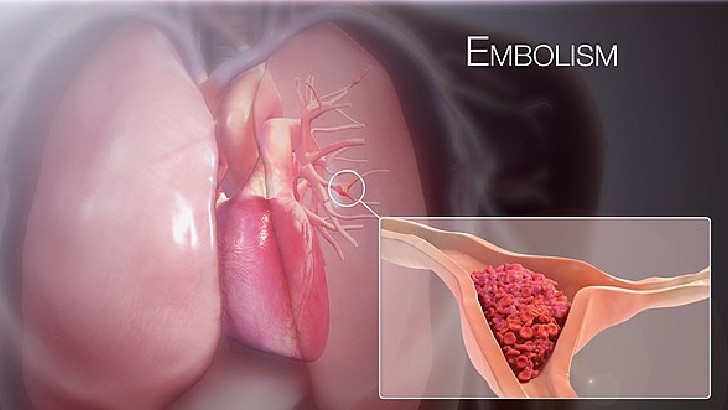

What is an embolism?

A circulating blood clot that becomes lodged in a vessel

A dilated blood vessel

A cancer of red bone marrow

The accumulation of plaque in arteries